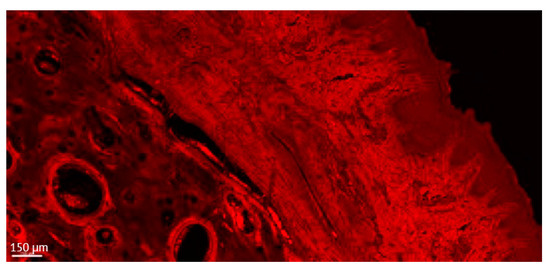

Figure 5.

Detailed aspect of the soft tissue and bone in a thick section of a non-ligated implant. Note the presence of acanthosis of the covering epithelium. ICT is present in contact with bone and implant, promoting an active bone resorption. (implant #2, oral aspect; bar, 150 µm).

The usual light microscopy technique using pentachrome stains revealed good tissue morphology preservation; however, the opacity of the metallic implant made it difficult on some of the specimens to properly identify the implant shoulder. The CLSM thin sections were easier to scan, having a flatter surface, yet the grinding to a thin section led to minor tissue cracks in the bone component (Figure 3A,B). Furthermore, the use of mounting medium and coverslip on the thin sections induced an additional decrease in contrast, altering the quality of soft tissue morphology in the thin sections (Figure 3A,B). In both thin and thick sections, the implant shoulder was easily identifiable, except in the thick sections where the implant was lost during histological processing. The peri-implant sulcus is shallower in non-ligated specimens than in ligated ones, the bone is in contact with the implant surface and the soft tissue is in contact with the healing abutment (Figure 4). Infiltrated connective tissue (ICT) was present in contact with bone and implant (Figure 5). However, it is important to mention that the cellularity of the ICT was not visible under CLSM; therefore, LM seemed better suited for the assessment of the ICT. Epithelial lining integrity was broken, more pronounced on the oral aspect, making the identification of landmarks like aJE extremely difficult (Figure 6). This comes not as a surprise under the severe inflammation circumstances found in peri-implantitis, as this landmark is poorly identifiable even on LM. In these areas of integrity loss, the highly inflamed soft tissue was identified in direct contact with the bone and implant (Figure 7). Regarding the soft tissues, the epithelial covering is clearly identifiable on both types of evaluation (LM and CLSM).

Early authors noted that a thickness of 80 to 100 µm (taking into account about 20 µm for the layer of glue or cement) should be sufficient for all the methods of microscopic examination of non-demineralized specimens and preparing thinner sections down to a thickness of 5 to 10 µm is, in most cases, unnecessary, requiring machine grinding and being associated with more risk of failure. However, they mentioned that thin sections (0.5 to 5 µm thickness) can provide additional information about cellular details of the implant-tissue interface [60]. In our study, such information was provided under CSLM by the “thick” sections (Figure 4).